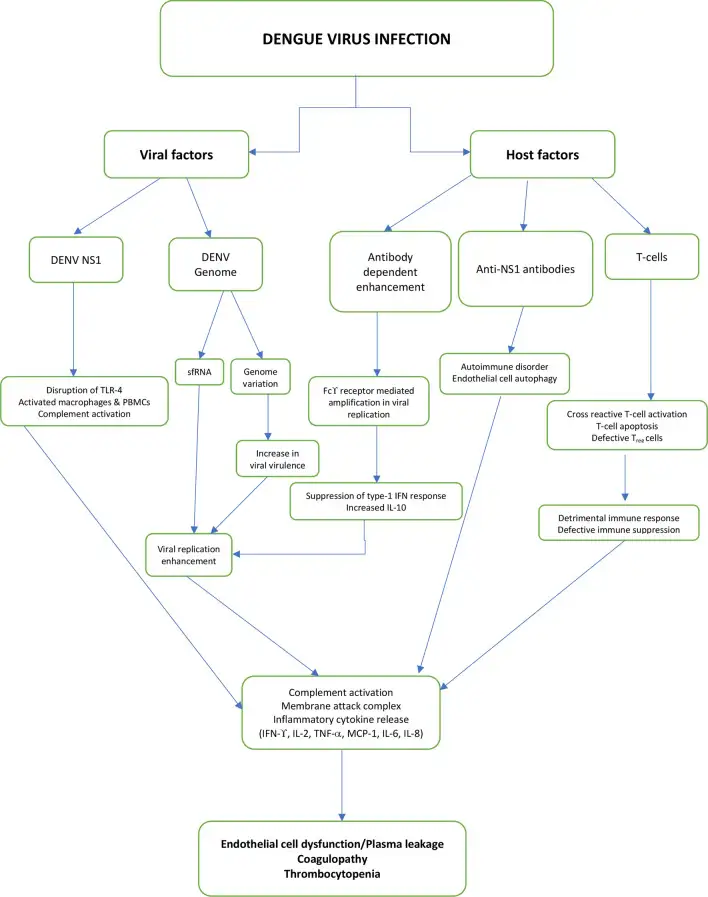

病毒的核心是一条约11千碱基的单股正链RNA,编码一个巨大的多聚蛋白。这个多聚蛋白会被切割成三种结构蛋白(C、prM、E)和七种非结构蛋白(NS1、NS2A、NS2B、NS3、NS4A、NS4B、NS5)。其中,NS1蛋白在登革热的致病过程中扮演着关键角色,它不仅参与病毒的复制,还能直接破坏血管内皮细胞,导致致命的血浆渗漏。

血管里的背叛:抗体依赖性增强的黑暗机制

登革热最令人费解的特征,是二次感染往往比初次感染更加严重。这在传染病史上几乎是独一无二的——通常情况下,初次感染后产生的抗体会为人体提供持久的保护。但登革热不同,它发明了一种邪恶的"借力打力"策略。

当一个人首次感染某种血清型的登革热病毒时,免疫系统会产生针对该血清型的特异性抗体。这些抗体能够有效地中和病毒,防止其感染细胞。然而,当同一个人后来感染另一种血清型的登革热病毒时,情况就会发生戏剧性的变化。原先产生的抗体虽然也能结合新的病毒,但无法有效地中和它。更糟糕的是,这些"非中和性抗体"会形成病毒-抗体复合物,然后通过抗体的Fc段结合到单核细胞和巨噬细胞表面的Fcγ受体上。

这种现象被称为"抗体依赖性增强"(Antibody-Dependent Enhancement,ADE)。通过这条通路,病毒获得了进入原本不易感染的免疫细胞的"后门"。研究表明,ADE可以使病毒在感染细胞中的复制效率提高100倍以上。更令人震惊的是,最近的研究还发现,当病毒通过ADE途径进入细胞后,它会主动抑制细胞的抗病毒反应,这一过程被称为"内在性ADE"。

血管渗漏的机制至今仍是活跃的研究领域。目前认为,登革热病毒的NS1蛋白起着核心作用。NS1可以激活补体系统,产生炎症介质;它可以诱导巨噬细胞释放大量促炎细胞因子,如白细胞介素-6(IL-6)和白细胞介素-8(IL-8);它还可以直接破坏血管内皮细胞之间的连接,增加血管通透性。此外,抗NS1抗体还可能与血管内皮细胞发生交叉反应,导致自身免疫损伤。